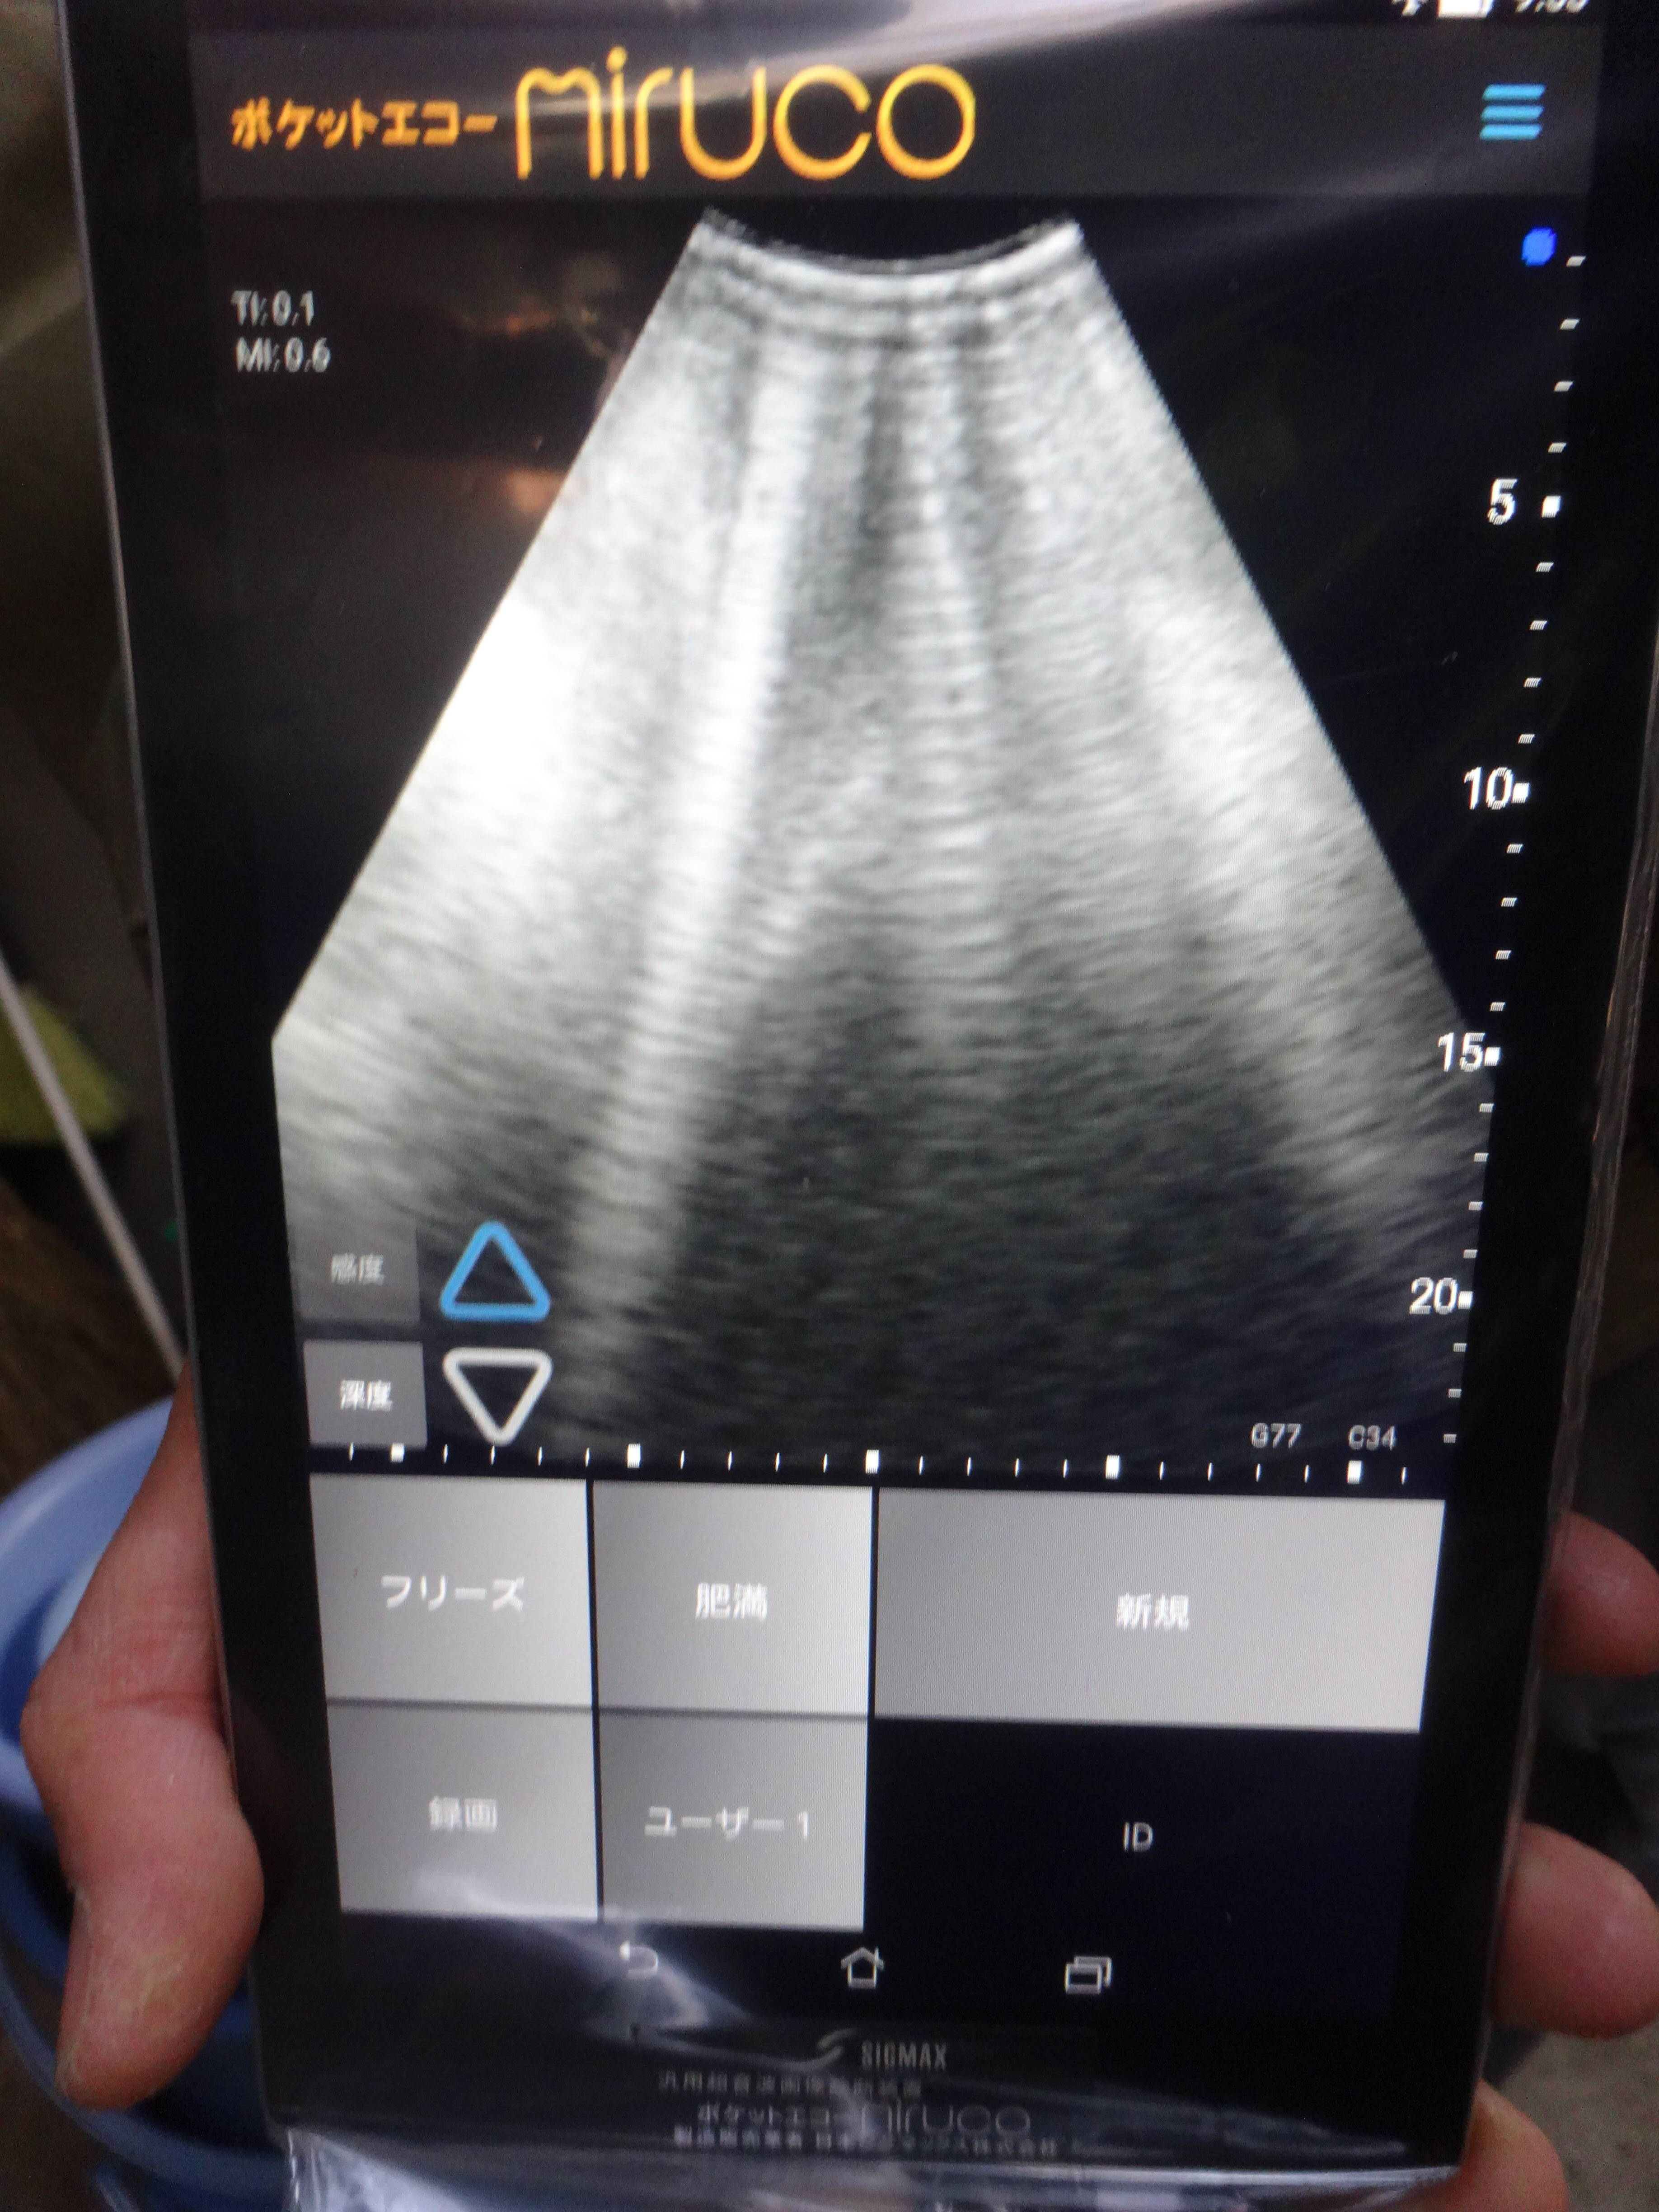

好物の餌を食べている間に、エコーのプローブをおなかに当てます。さすがに嫌がるかと思いましたが、何事もなく食べ続ける姿にどっしりとした大物感を感じました(笑)。

しかし、厳しい寒さから身を守るためのオオツノヒツジの冬毛は、エコーの超音波を阻み、まったく画面に映りません。かわいそうですが、一部の毛を刈ることにしました。毛がないところがありますが、病気ではないのでご安心ください。

ようやく見えたおなかの画像には赤ちゃんらしきものが!熟練の獣医さんは胎児の心拍も確認できたようです。正直、私にはよくわかりませんでしたが...。